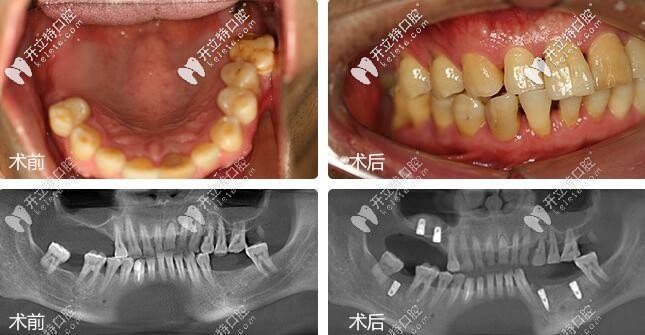

鄭蒼尚院長(zhǎng)微創(chuàng)種植牙案例▼